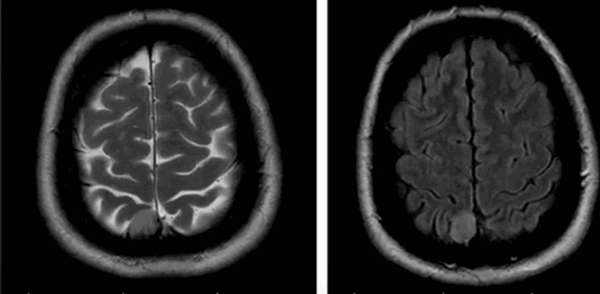

Признаками рассеянного склероза головного и спинного мозга на МРТ изображениях будут:

- слабовыраженные очаговые изменения, повышение сигнала Т2;

- типичное вовлечение спинного мозга;

- распространенность не более двух сегментов;

- поражения латеральных или задних столбов белого вещества с возможным вовлечением центральных отделов;

- в острой фазе утолщение спинного мозга;

- в хронической фазе слияний очагов;

- атрофические изменения в мозге - заместительная гидроцефалия.

| Признаки РС на МРТ | Норма и очаги рассеянного склероза на МРТ снимках |